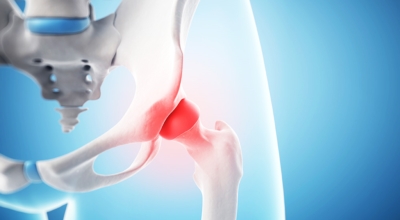

앞뒤로 움직이는 무릎 관절과는 다르게 고관절은 앞뒤 뿐만 아니라 좌우, 회전 등 자유롭게 움직임이 가능하며 운동 범위가 큰것이 특징입니다. 우리 몸 중 가장 큰 관절이기도 하다. 고관절에서 발생할 수 있는 고관절 통증 증상에 대해 알아보겠습니다.

고관절염은 고관절에 발생하는 관절염을 말하며 고관절의 연골이 닳게 되면서 뼈와 뼈가 서로 부딪히며 통증을 유발하게 됩니다. 고관절염 초기 증상으로는 사타구니 부위가 불편하게 느껴지며, 무리하면 통증이 발생할 수 있고 관절염 증상이 악화되면서 사타구니에서 느끼던 통증이 허벅지와 엉덩이 통증으로 이어지기도 하는데요 고관절염 통증 증상으로 초기에는 허리 통증이 나타나 허리 질환과 혼동하기 쉬우며 특히 척추질환이 있는 사람은 고관절 통증 증상과 마찬가지로 엉덩이, 다리 통증이 동반되기 때문에 더욱 헷갈리는 경우가 많다고 합니다.